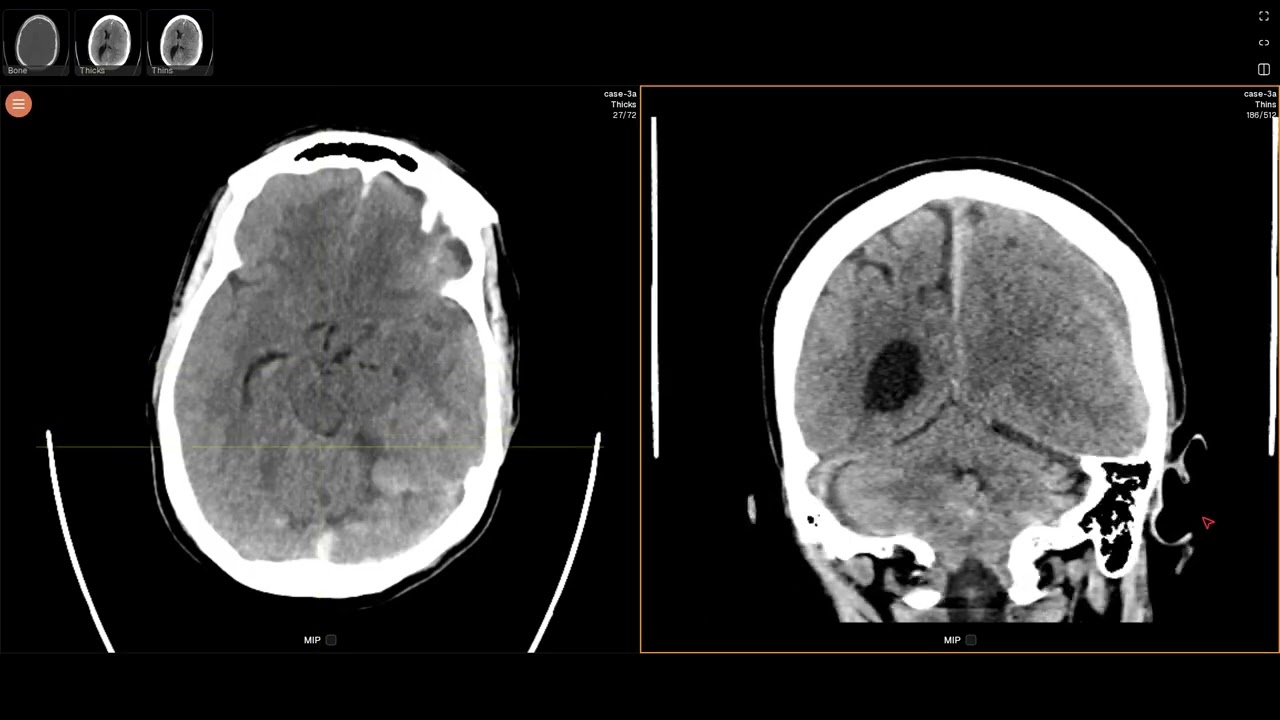

Subdural hematoma (EDNeurorad Case 3a)

Imaging findings:

There is a predominantly hyperdense left cerebral convexity subdural hematoma. Near the vertex, there is a layering hematocrit level, typically seen in the setting of either active bleeding or coagulopathy. The hematoma results in mass effect as evidenced by effacement of the left lateral ventricle compared to the right and midline shift.

As nicely seen on the coronal reformations from the thin section data, the hematoma has components along the left tentorium and the falx. These can also be seen on the axial images.